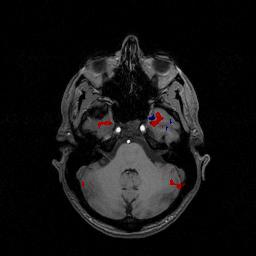

首先是在宏观层次上对脑的研究,就像是下方这幅图上展示的,用磁共振成像来对不同脑结构之间的神经活性进行观测。